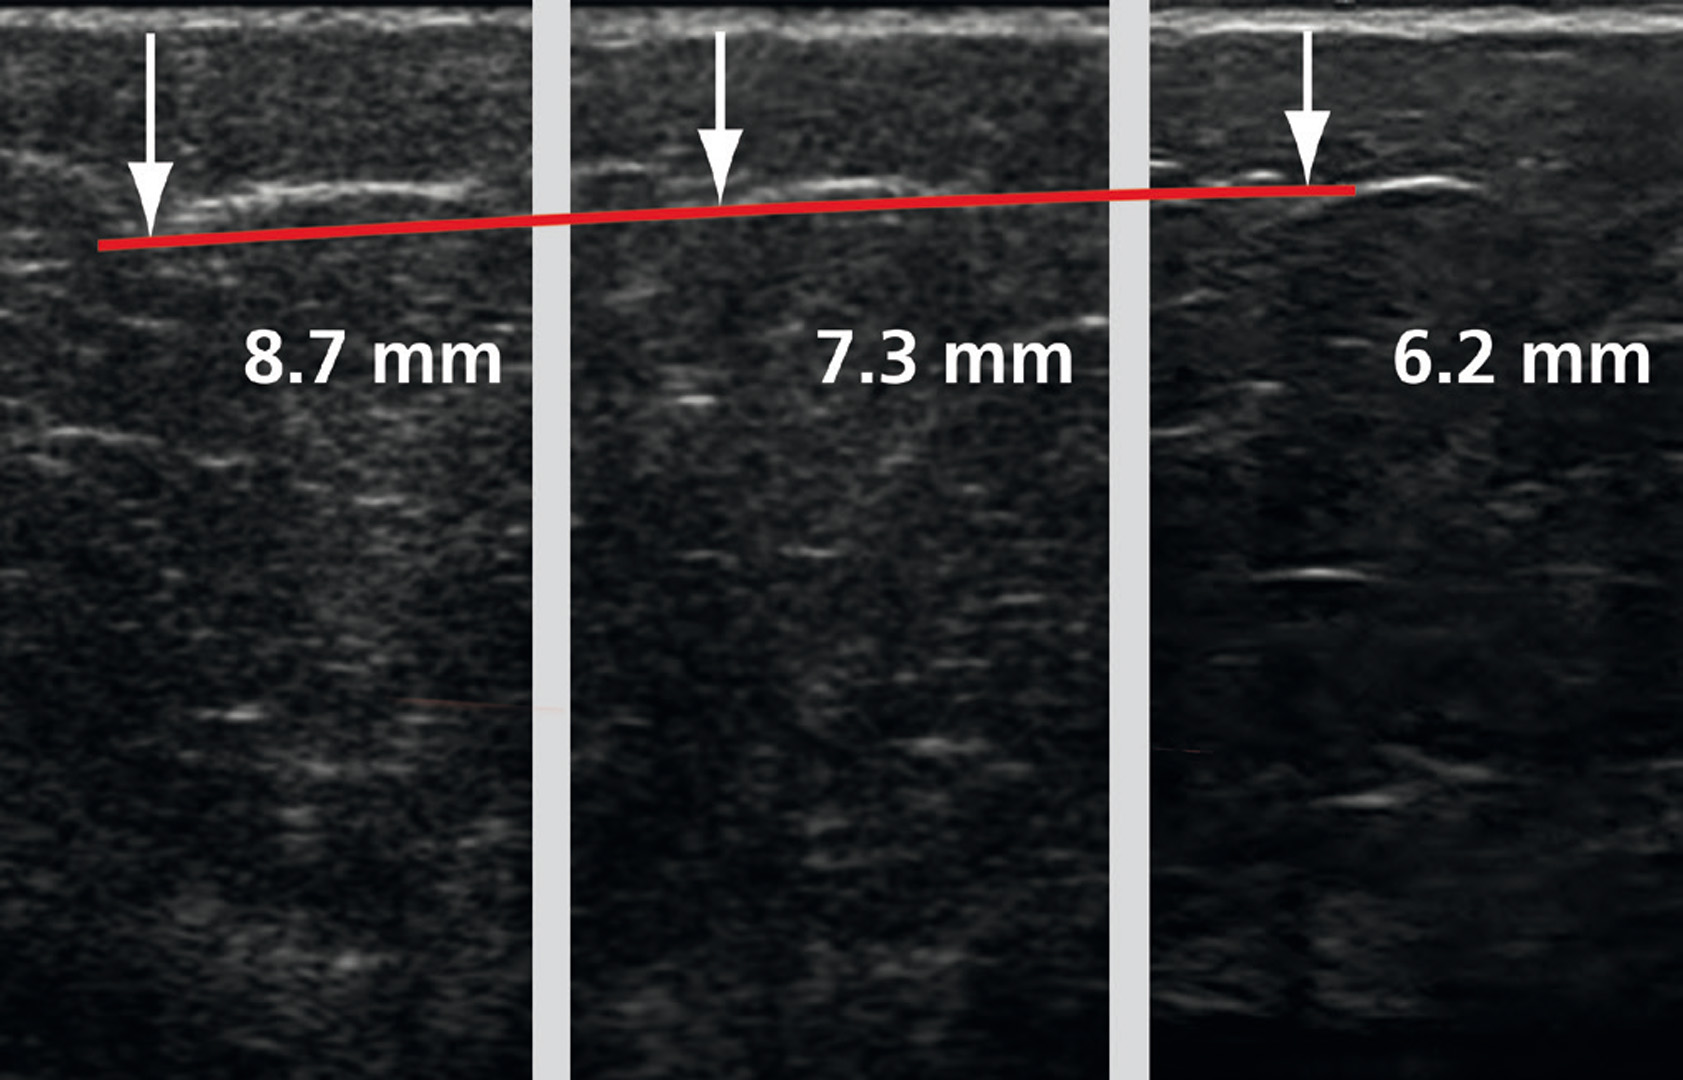

- Radiální rázová vlna se aplikuje na oblasti v blízkosti povrchu kůže pro účely, jako je zlepšení elasticity pojivové tkáně nebo ošetření celulitidy.